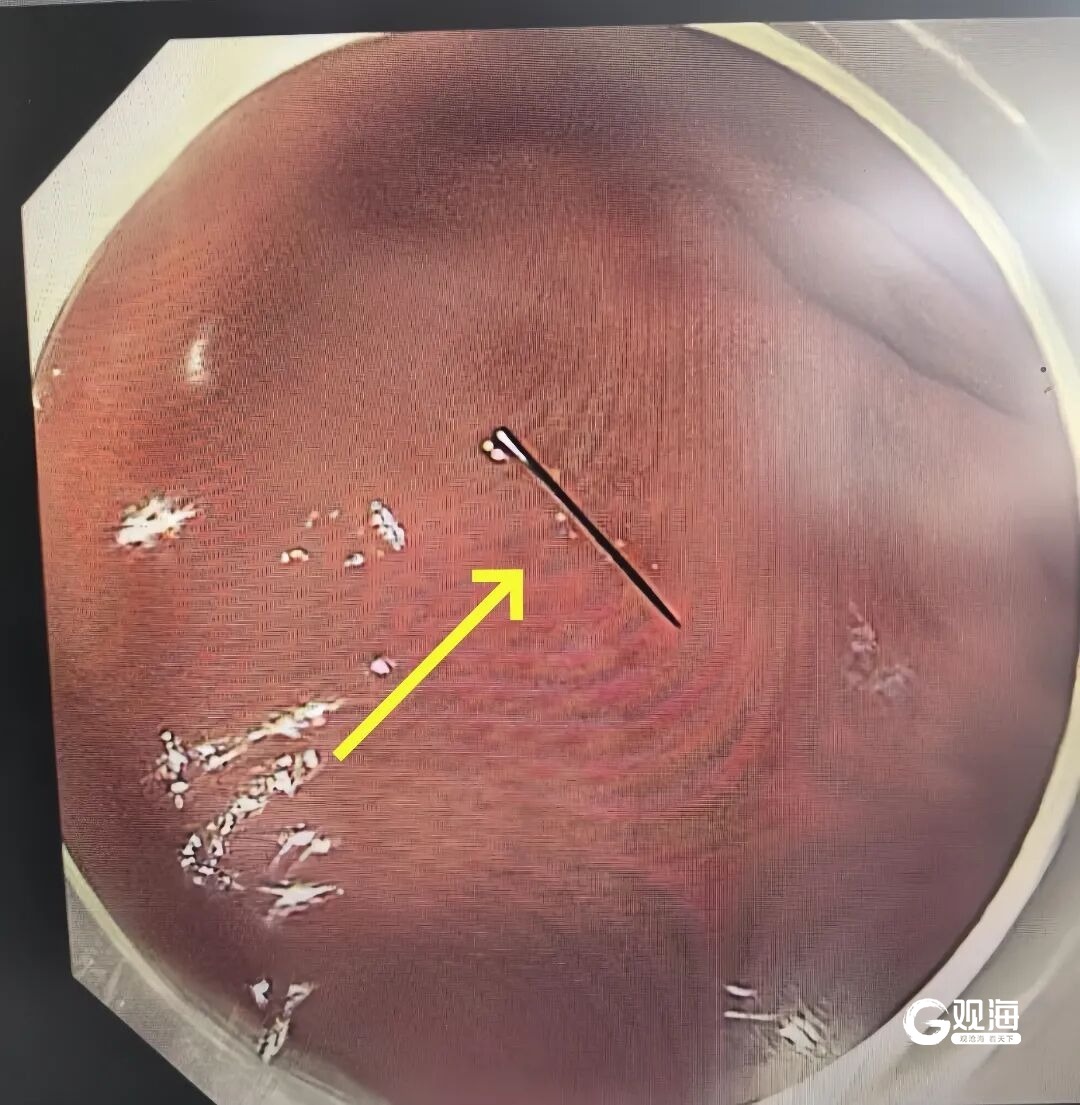

消化内科、内镜中心医护团队立刻响应。大家从家中连夜出发,在最短时间内集结到位。凌晨3点,术前准备就绪,一场全麻下胃镜异物取出术正式开始。凭借丰富的儿童内镜经验,手术仅用10余分钟就顺利完成,那截约1厘米长的断针被完整取出。

万幸的是,断针尚未刺破胃黏膜、未造成出血损伤。当医生将取出的断针展示在家人面前时,一直悬着的心终于落地。术后欣欣恢复顺利,状态平稳,目前已康复出院回家。